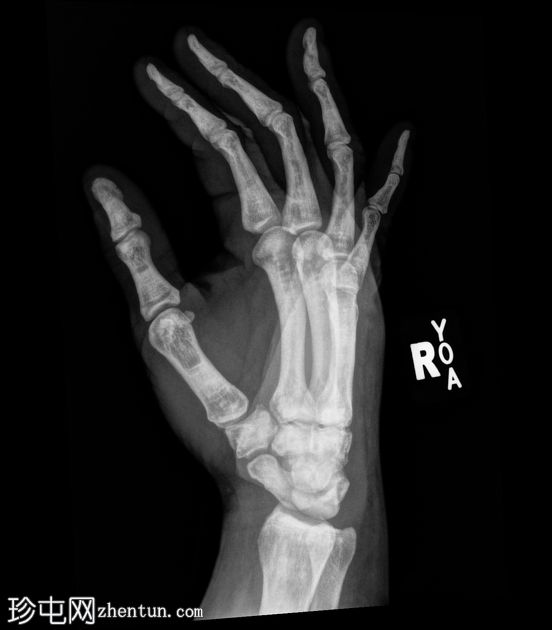

X线片

正位

斜位

弥漫性骨硬化,符合骨硬化症病史。骨中骨征。无急性骨折。